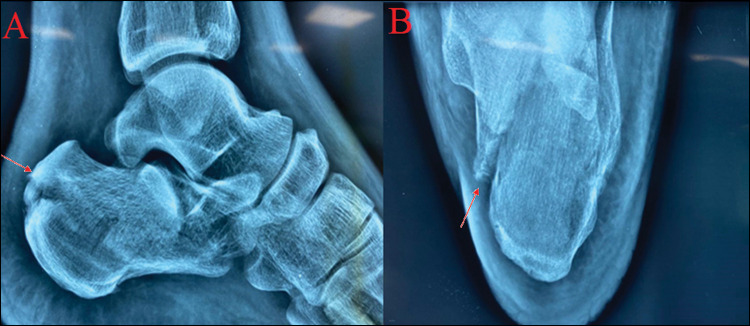

Materials and methods: Thirty-two patients (40 ft) with displaced intra-articular calcaneus fractures (10 were of Sanders type II, 16 were of type III, and 14 were of type IV) were treated between January 2018 and September 2021. All patients were managed surgically with open reduction and internal fixation using lateral extensile approach combined with de-roofing of the lateral wall. All patients were followed up for ≥1 year using functional parameters American Orthopaedic Foot and Ankle Score (AOFAS), visual analogue scale (VAS) and radiological parameters (Bohler angle, Gissane angle, height of the calcaneus, width of the calcaneus and pitch of calcaneus).

Results: Out of 32 patients, one patient lost to follow-up. At 1 year follow-up, mean AOFAS hindfoot score was 86.2 ± 5 (Sanders type II: 91.2, Sanders type III: 87.6, and Sanders type III: 81.4), mean VAS score was 91.3 ± 2.1, mean Bohler angle (°) was 27.2 ± 4.7, mean Gissane angle (°) was 136.4 ± 5.2, mean calcaneus height was 46.2 ± 2.1 mm and mean calcaneus width was 45.1 ± 3.2 mm. Patients with decreased Bohler angle between postoperative images and follow-up had lower AOFAS hindfoot scores. Complications included persistent swelling (64.10%), stiffness (33.33%), superficial infections (5.12%), and wound dehiscence (10.25%).

Conclusion: Lateral wall de-roofing is a useful technique which allows the lateral wall to get flattened reducing soft tissue complications and providing bone graft as well. This approach also adequately exposes fracture fragments, subtalar and calcaneocuboid joints for good anatomical reduction. Hence, it can act as a useful adjunct in the internal fixation of intra-articular calcaneus fractures.